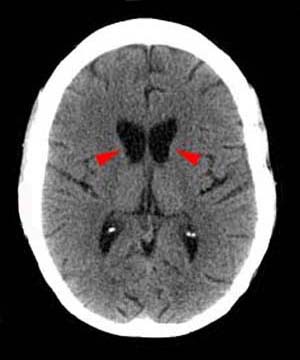

eye of the tiger sign

globus pallidus T2 hypointensity with central hyperintensity

PKAN

iron deposition disorder